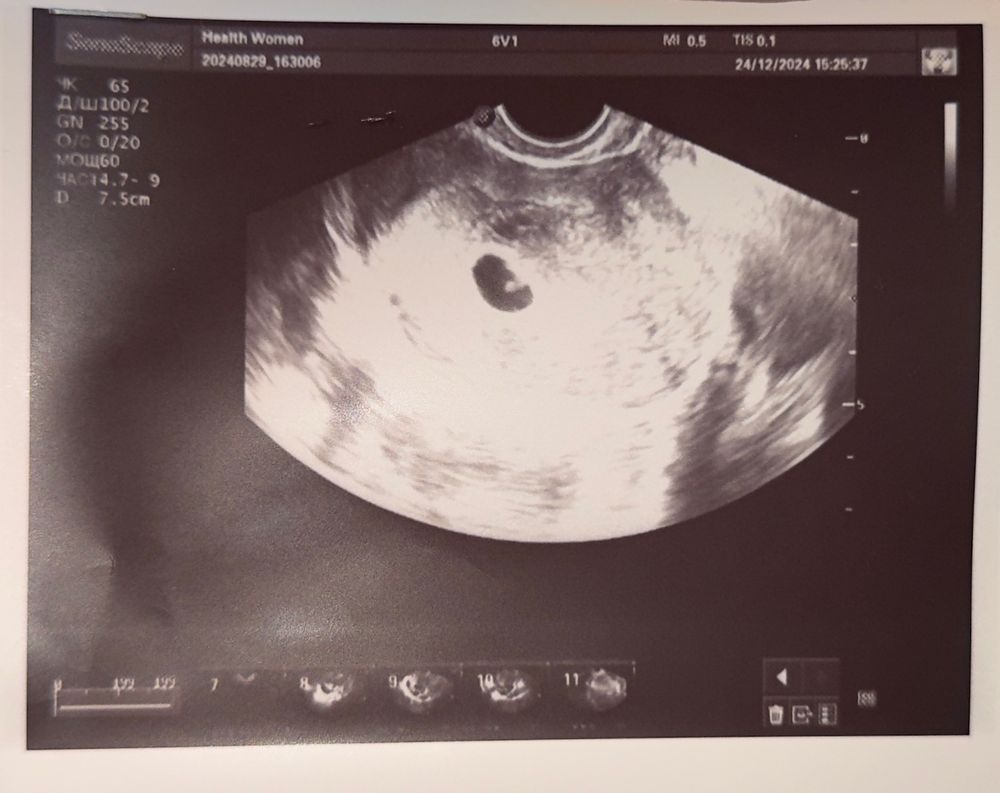

Марина в ЭКО-мама год 22дпп первое УЗИ🥰 Результаты УЗИ Пя 11мм, жм 3мм, ктр эмбриона 2мм + сердцебиение Расскажите как у вас было на таком сроке ? Посмотрите еще 20 записей на эту тему Отменить Ответить Ольга 22 дпп ПЯ 13 мм, жм и эмбриона еще не видели. в 25 дпп на другом аппарате пя 18 мм, ктр 2 мм, пульсация 24.12.2024 Ответить Ирина На 22 дпп было пя 16 мм и жм 3,3 мм, 30.12 идем смотреть эмбрион и сердечко слушать, будет 35 дпп 24.12.2024 Ответить Мария На 23 ДПП было ПЯ 10, жм 3,5 ктр 1,5, сердечко не смотрели еще 24.12.2024 Ответить Анна На 23 дпп только пя 14 и жм 3 На 30 увидели все что нужно) 24.12.2024 Ответить Экспертное УЗИ. Итоги. 23 дпп узи Чаты Беременных Выберите чат: Январята-2026 Февралята-2026 Мартята-2026 Апрелята-2026 Майчата-2026 Июнята-2026 Июлята-2026 Августята-2026